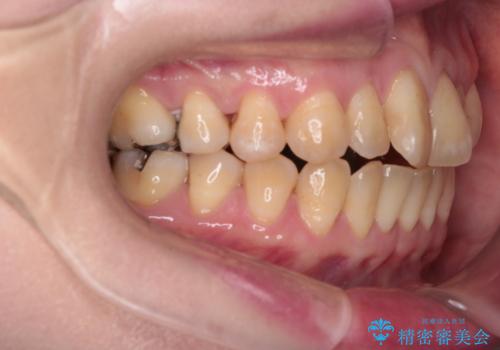

【インビザライン】前歯の捻れとオープンバイト

- 上の前歯の捻れと、前歯で物が噛めないことを主訴に来院されました。

前歯の翼状捻転とオープンバイト傾向だったため、インビザラインにて矯正を行いました。右下の奥歯は保存不可だったため、抜歯を行いインプラントにて修復を行なっています。

翼状捻転はインビザラインでは苦手とする動きですが、ここまで綺麗に治すことができました。